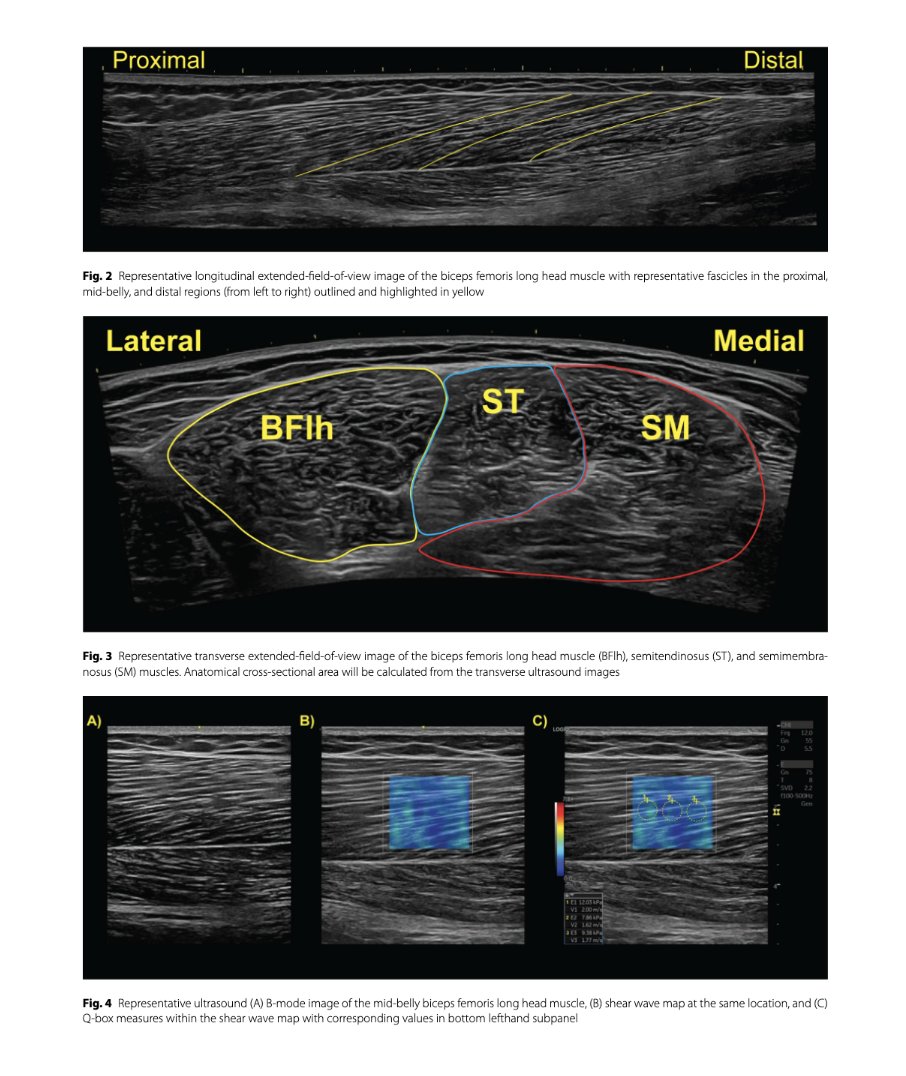

🔝"The study protocol investigated the effects of a 6-week training program using either the hip-dominant Romanian deadlift or Nordic-HE on hamstring strain injury risk factors & sprint performance" 👉S. Crawford et al, 2023 🇺🇸 BMC Series 📂Open Access: …sportsscimedrehabil.biomedcentral.com/articles/10.11…